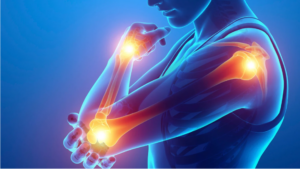

De l’épaule au pouce : analyser la douleur et orienter le patient en orthopédie

Affûtez votre analyse des douleurs du membre supérieur et orientez vos patients vers l’orthèse la plus adaptée pour un conseil expert et sécurisant au comptoir.

Affûtez votre analyse des douleurs du membre supérieur et orientez vos patients vers l’orthèse la plus adaptée pour un conseil expert et sécurisant au comptoir.